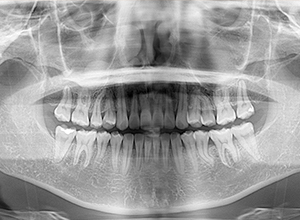

初診時

FP・IOP

X-Ray

X-Ray所見

パノラマ所見 左右上5、左下5に歯根の湾曲が認められた。上下顎左右側8は抜去済みであった。